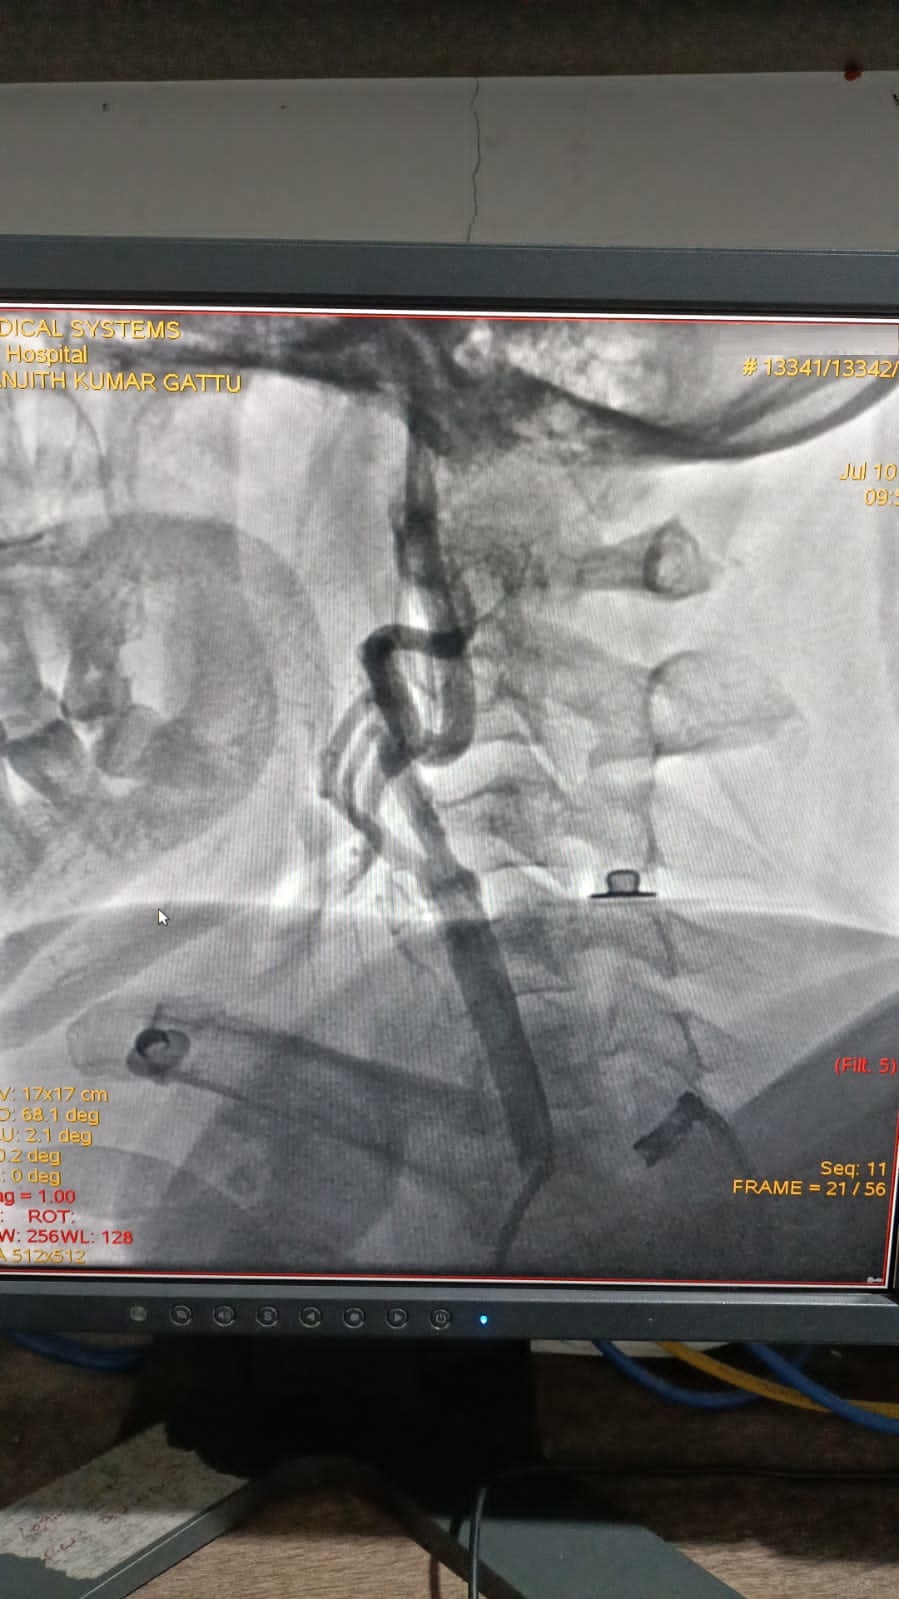

Left Coronary Diseased Artery